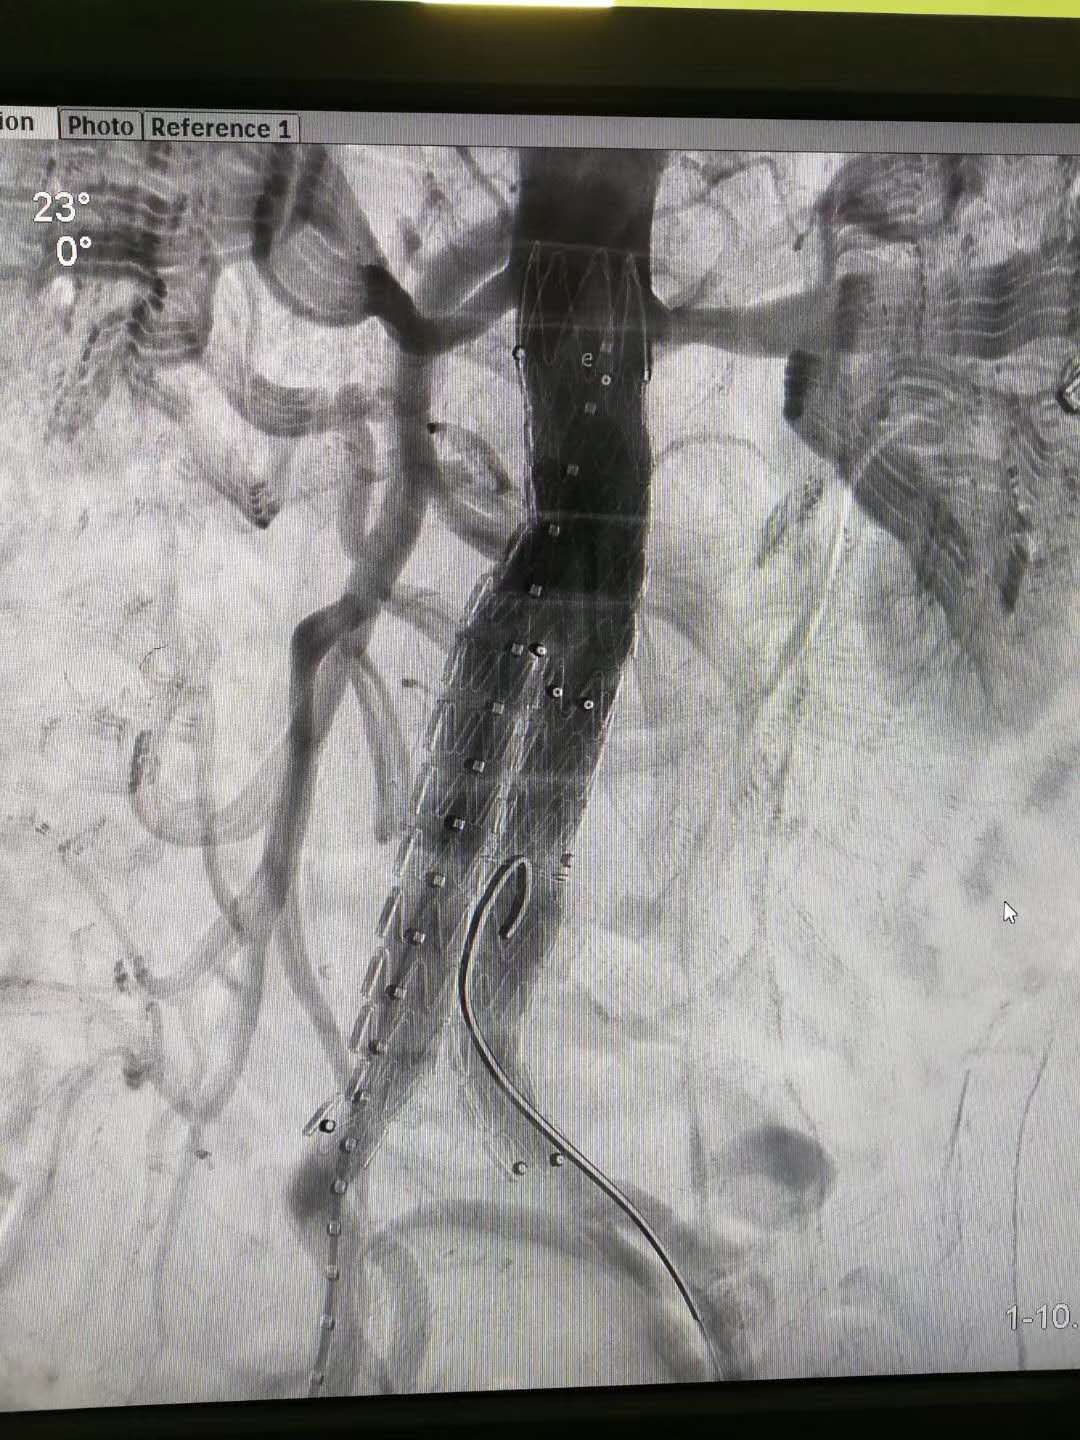

一例75岁男性患者3年前诊断腹主动脉瘤,3周前复查发现动脉瘤增大。近日我院成功为其行局部麻醉+强化麻醉下的全微创腹主动脉瘤修复术。只有两个长度0.5cm的手术切口,无需气管插管麻醉,手术时间一个小时,术后无需ICU过渡,恢复极快。除了造影时呼吸不易控制外几乎找不到缺点了。术后该患者恢复良好,已康复出院。